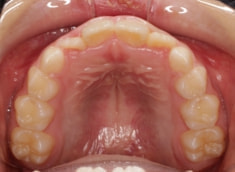

小児期ケース:叢生(ガタガタ)

治療法:拡大プレート+フルパッシブブラケット(クリアスナップ)

治療前